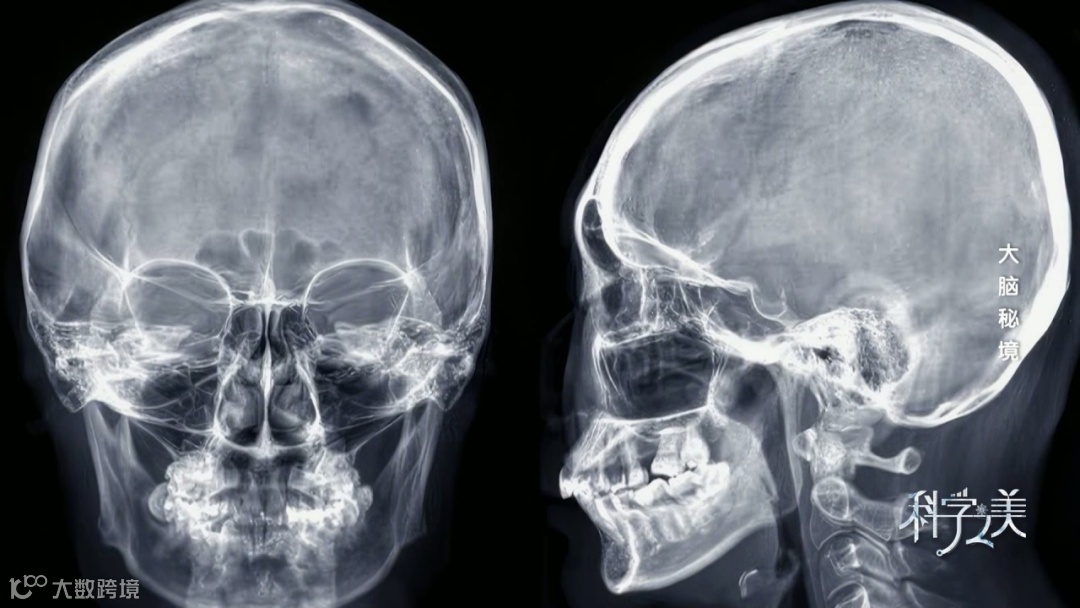

如此庞大的神经网络构成了神奇的大脑,虽然它的重量仅占身体的2%,却消耗着全身20%的能量,而它的高效运转,依赖着一条隐藏在颅骨之下的“生命之河”——脑血管系统。

在人类漫长的进化过程中,不断增加的大脑重量使得脑血管比其他动物更加密集。如果把所有脑血管连在一起,总长度达到16亿米,相当于从地球到月球距离的四倍。

“大家现在看到的这些标本,都是我们人体的真实的标本制作的铸型标本。”首都医科大学基础医学院人体解剖与组织胚胎学系解剖教研室主任高艳说,标本上的蓝色代表静脉,红色代表动脉。从血管铸型可以看到,脑的血管是非常密集的。与其他部位同级别的血管直径相比,进入脑部的血管直径更细。

作为供养生命智慧的通道,脑血管超长且纤细。更与众不同的是,大脑被设计成没有运动的器官,它不像心肺、肠道那样能跳动、膨胀或收缩。因此,缺乏运动的大脑血管壁比身体其他部分血管壁更薄。

高艳解释,脑的血液主要是由颈内动脉和椎动脉两大血管来供应,这两个血管进入颅内,提供脑的血液和营养。脑控制着我们的运动、感觉以及情感,它需要非常丰富的血液供应,因此脑的血管十分密集。

伦琴发现的X射线,实现了人体内部结构的成像,这让医学家们欢欣鼓舞。借助X射线,人们通过颅骨的变形情况大致推测病变位置,但是这种间接的影像对于脑部血管的成像不够理想。